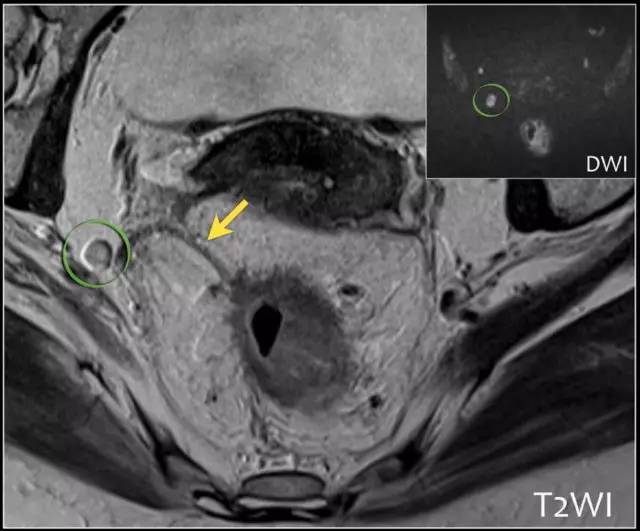

基于形状、边界和信号强度的标准已经被证明是更可靠的。使用这些标准,与组织病理学评估相比,MRI 确定淋巴结受累的准确度为 85%。然而阴性 MRI 成像不能排除淋巴结转移,因为成像技术不能确定淋巴结内的微转移。

以下是淋巴结分期诊断线索:

1. 均匀的淋巴结小于 10 mm,具有均匀信号强度不可疑。

2. 具有不规则边界和/或混合信号强度是可疑的。

3. 存在 1~3 个可疑淋巴结是 N1,存在 4 个或更多个是 N2。

4. 必须报告位于 CRM 1 mm 以内的任何淋巴结,因为它高度可疑 CRM 阳性。

图 25 DWI 有助于检测淋巴结